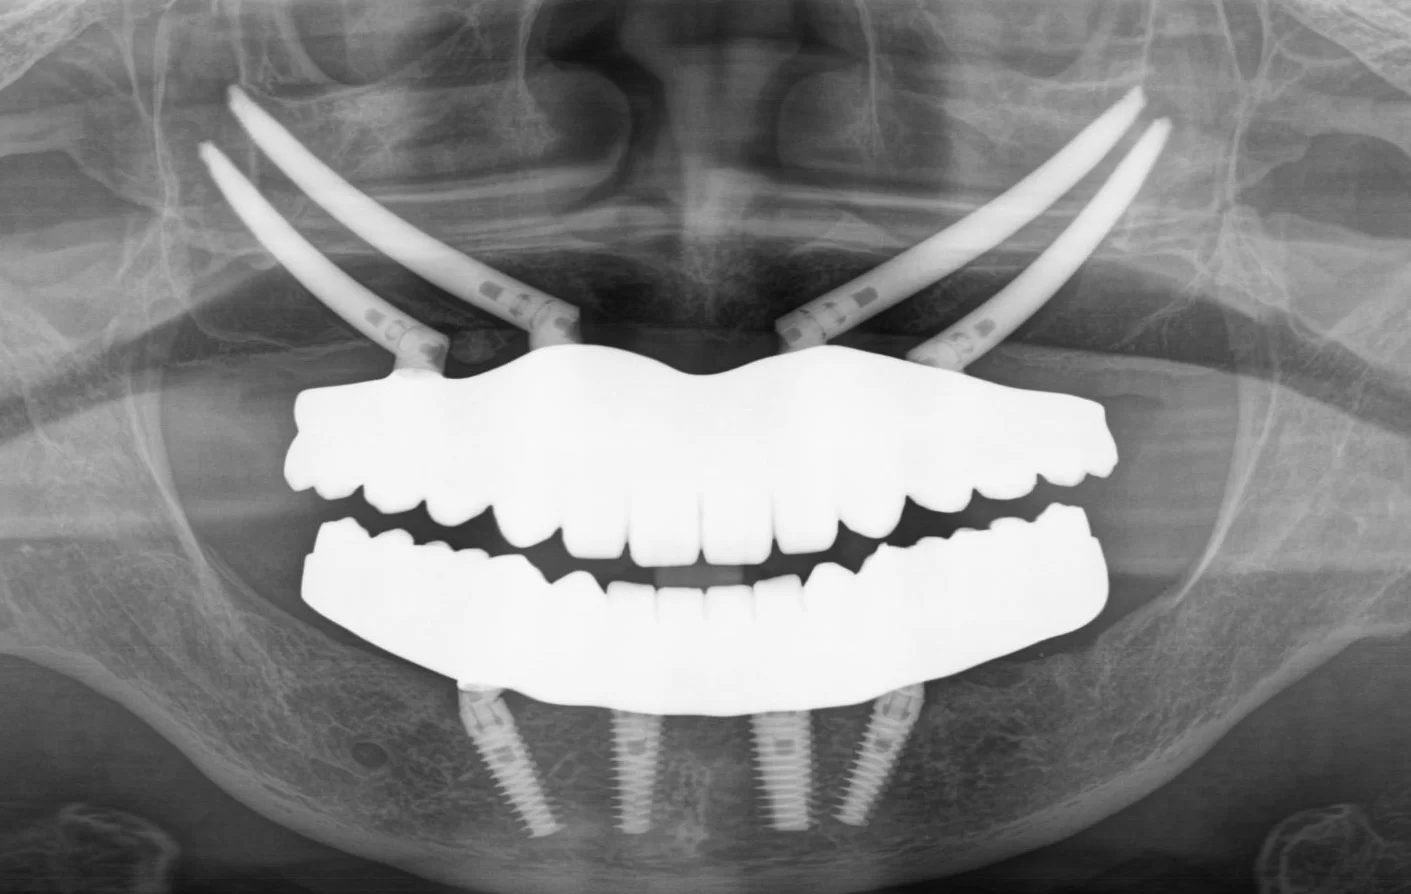

術後

内容 :上下顎オールオン4ザイゴマ4

費用 :6,132,800円

※モニター価格

期間 :半年

リスク:出血・腫れ・痺れ・痛み

手術は計画通り進行し、術後の仕上がりにもとても満足しています。

長年苦しめられた義歯による痛みや不自由さから解放され、食事を楽しめるようになることが楽しみです。美しい見た目になったのでマスクを外して過ごせるようになることも嬉しいです。自分と同じように歯の悩みで苦しむ方にぜひ勧めたいです。